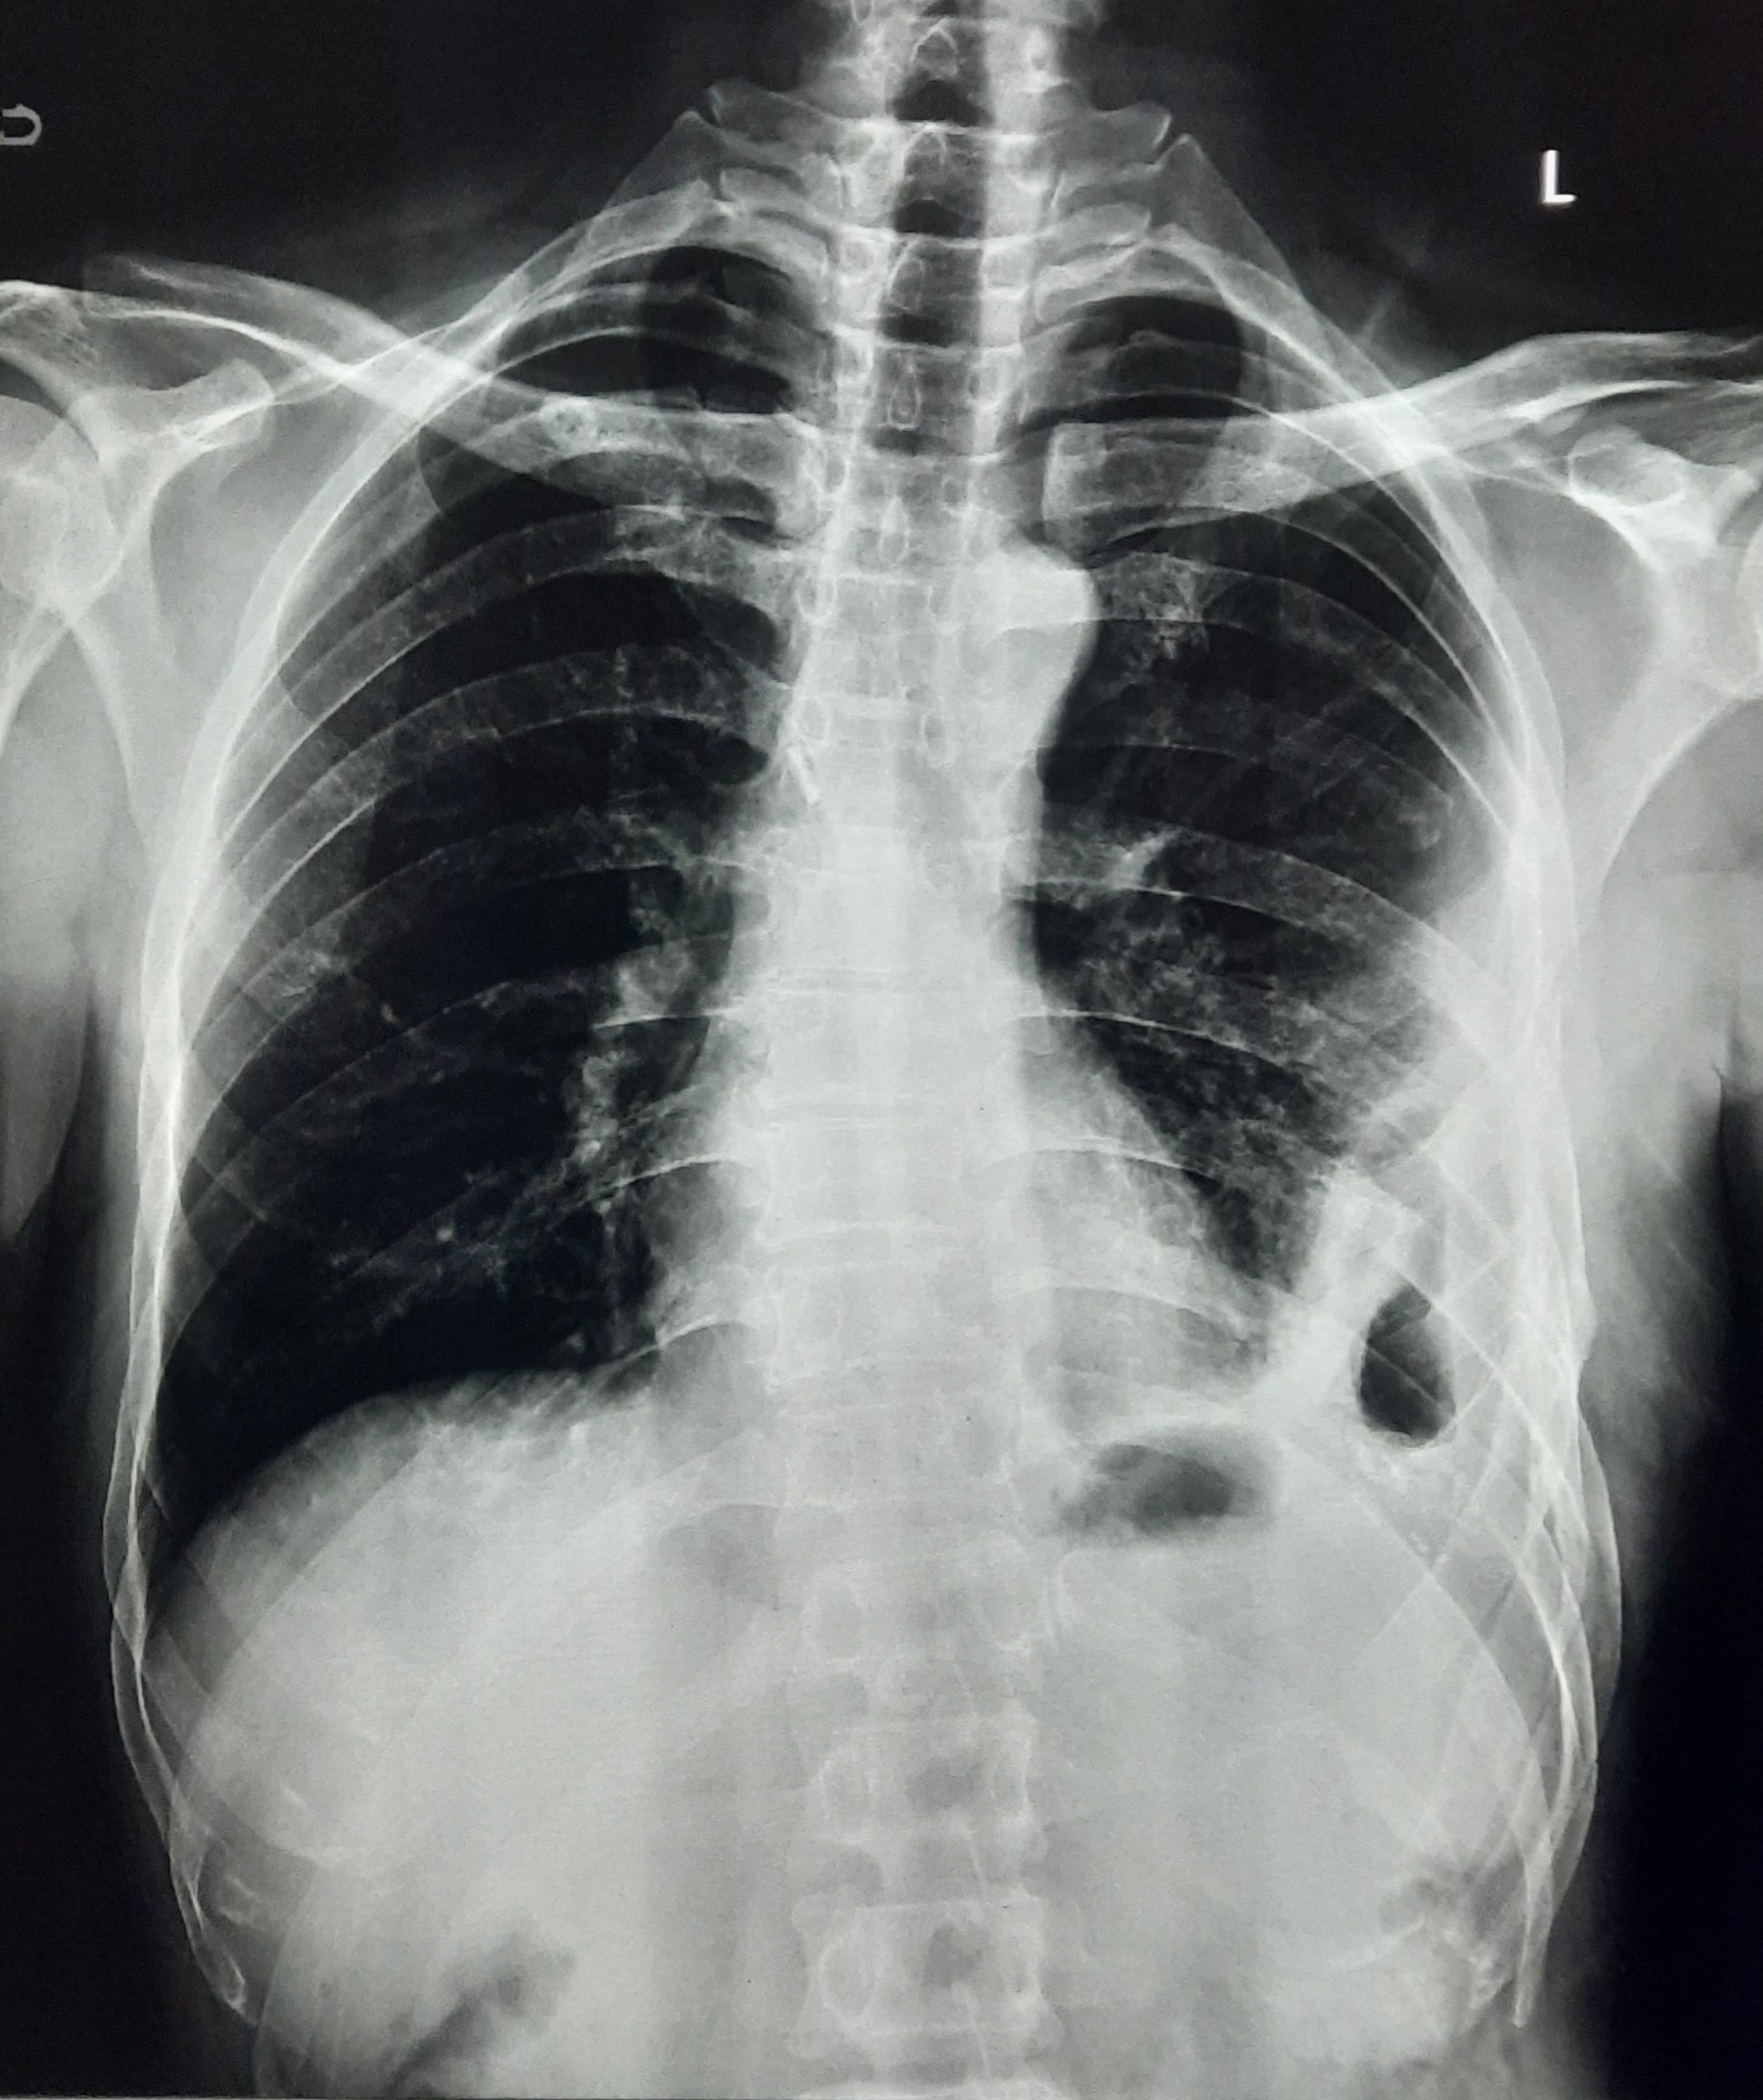

| 149 | IGGMC, Nagpur, Nagpur | P2 | 29-4323 | Samina Parveen | Consent taken on Paper | 30 Yrs. |

Provisional Diag : Bilateral Tubercular Pleural Effusion

Final Diag : Bilateral Tubercular Pleural Effusion With Right Sided Pigtail Infiltration |

TB Case (Confirmed) | Bilateral CP Angle Blunting With Bilateral Homogenous Opacity Left Zone With Pigtail Right Pleural Effusion | Abnormality visible on x-ray |